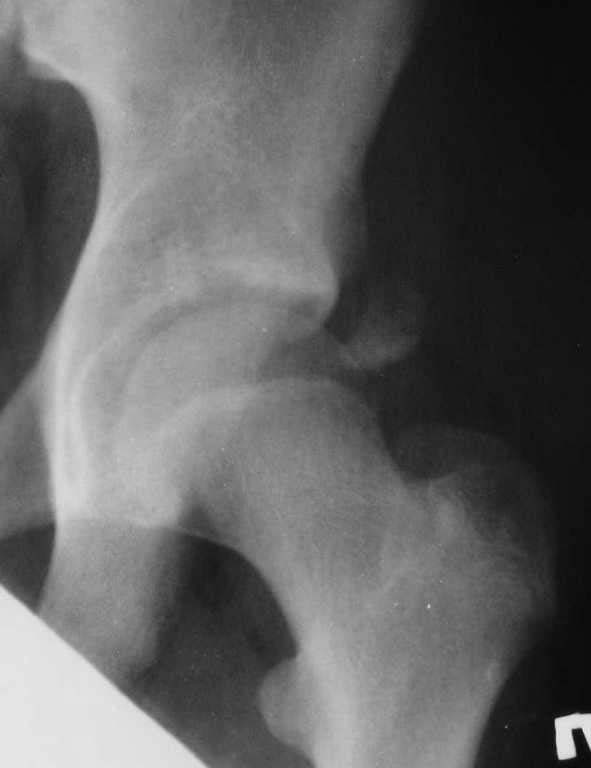

День добрый! Мальчик, 14 лет. Травма во время игры в футбол - отрывной перелом spina iliaca anterior inferior.

Пальпаторно боль в проекции ости. Ограничение сгибания-разгибания бедра из-за боли. Какова тактика лечения? Заранее благодарю! С уважением, А.В.Владзимирский Донецкий НИИ травматологии и ортопедии